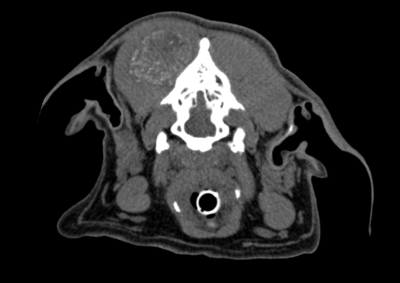

腫瘍外科 注意 ボタンをクリックした先に、治療中および手術中の画像が説明で使用されている場合がございます。 そのような画像に弱い方は閲覧なさらないようお願いいたします。 腫瘍外科 犬の甲状腺癌 軟部組織外科腫瘍外科 唾液腺癌 Salivary gland carcinoma 軟部組織外科腫瘍外科 胃部分切除術・ビルロートI 腫瘍外科 MLO 多小葉性骨腫瘍 腫瘍外科 軟部組織肉腫 G3 軟部組織外科腫瘍外科 直腸プルスルー 内科腫瘍外科 尾状葉乳頭突起に限局した高分化型肝細胞癌 内科腫瘍外科 猫の消化管型リンパ腫(腸穿孔を伴う) 腫瘍外科救急・集中治療 腹腔内出血 内科腫瘍外科救急・集中治療 細菌性腹膜炎 腫瘍外科 肝臓原発血管肉腫 腫瘍外科 犬の原発生肺癌(左) <1234567> 症例カテゴリー 放射線治療整形外科軟部組織外科脳神経外科内科腫瘍外科救急・集中治療リハビリテーション科腫瘍内科内視鏡科脳神経科呼吸器外科中医・漢方猫の腎移植循環器科